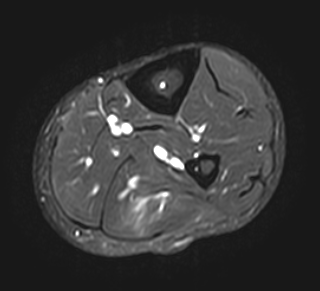

MRI

Grade 2b lateral soleus